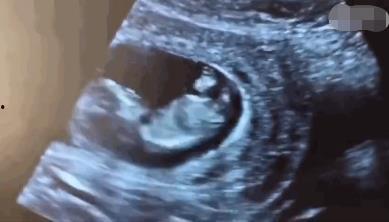

亲爱的读者们,你是否曾好奇过生命的起点?那是一个神奇而神秘的时刻,一个微小的生命在母体中悄然诞生。今天,我要带你走进一个全新的世界——胚胎视频,让我们一起见证生...